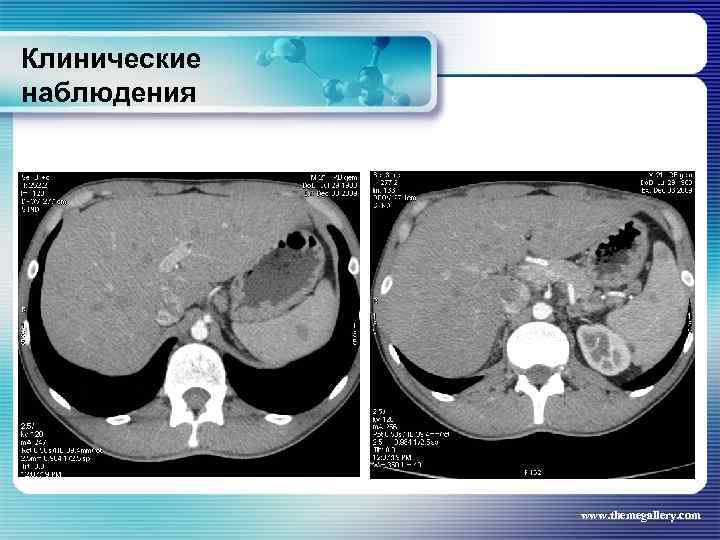

Клинические наблюдения Больной Б. , 1990 г. р. С лета 2008 года увеличены лимфатические узлы на шее. Не обследовался. В течение полугода нарастание слабости, снижение работоспособности, повышение температуры до 38°С, с ознобами и профузными потами. Госпитализирован по месту жительства, а затем в гематологическое отделение. В отделении 02. 2009 г. выполнена биопсия шейного лимфатического узла: лимфома Ходжкина, смешанно-клеточный вариант. При лабораторном исследовании выраженные признаки биологической активности процесса, резко измененные «печеночные» пробы. При лучевом исследовании (рентгенография, СКТ, УЗИ) выявлены признаки поражения внутригрудных, абдоминальных лимфатических узлов, позвонков. www. themegallery. com

Клинические наблюдения Больной Б. , 1990 г. р. С лета 2008 года увеличены лимфатические узлы на шее. Не обследовался. В течение полугода нарастание слабости, снижение работоспособности, повышение температуры до 38°С, с ознобами и профузными потами. Госпитализирован по месту жительства, а затем в гематологическое отделение. В отделении 02. 2009 г. выполнена биопсия шейного лимфатического узла: лимфома Ходжкина, смешанно-клеточный вариант. При лабораторном исследовании выраженные признаки биологической активности процесса, резко измененные «печеночные» пробы. При лучевом исследовании (рентгенография, СКТ, УЗИ) выявлены признаки поражения внутригрудных, абдоминальных лимфатических узлов, позвонков. www. themegallery. com

Клинические наблюдения www. themegallery. com

Клинические наблюдения www. themegallery. com

Клинические наблюдения Тот же пациент Был сформулирован клинический диагноз: Лифома Ходжкина, нодулярный склероз IV B стадия с поражением шейных, надключичных, подчелюстных, подмышечных, переднегрудных, парастернальных, паховых, внутригрудных, абдоминальных лимфатических узлов, печени, костного мозга, позвонков. В связи с выраженной нарастающей интоксикацией была начата терапия преднизолоном и первый цикл ВЕАСОРР. на этом фоне появились: резко повышенные показатели трансаминаз, асцит, массивные белковые отёки, сохранилась опухолевая интоксикация. Развилась аплазия гемопоеза. Доза преднизолона была увеличена. На этом фоне развилась полисегментарная грибковая пневмония. www. themegallery. com

Клинические наблюдения Тот же пациент Был сформулирован клинический диагноз: Лифома Ходжкина, нодулярный склероз IV B стадия с поражением шейных, надключичных, подчелюстных, подмышечных, переднегрудных, парастернальных, паховых, внутригрудных, абдоминальных лимфатических узлов, печени, костного мозга, позвонков. В связи с выраженной нарастающей интоксикацией была начата терапия преднизолоном и первый цикл ВЕАСОРР. на этом фоне появились: резко повышенные показатели трансаминаз, асцит, массивные белковые отёки, сохранилась опухолевая интоксикация. Развилась аплазия гемопоеза. Доза преднизолона была увеличена. На этом фоне развилась полисегментарная грибковая пневмония. www. themegallery. com

Клинические наблюдения www. themegallery. com

Клинические наблюдения www. themegallery. com

Клинические наблюдения www. themegallery. com

Клинические наблюдения www. themegallery. com

Клинические наблюдения www. themegallery. com

Клинические наблюдения www. themegallery. com

Клинические наблюдения www. themegallery. com

Клинические наблюдения www. themegallery. com

Клинические наблюдения Тот же пациент Антибактериальная терапия была не эффективна, на фоне противомикробной терапии (вифендом) достигнут положительный эффект, больной переведен на другую программу химиотерапии (ABVD) www. themegallery. com

Клинические наблюдения Тот же пациент Антибактериальная терапия была не эффективна, на фоне противомикробной терапии (вифендом) достигнут положительный эффект, больной переведен на другую программу химиотерапии (ABVD) www. themegallery. com